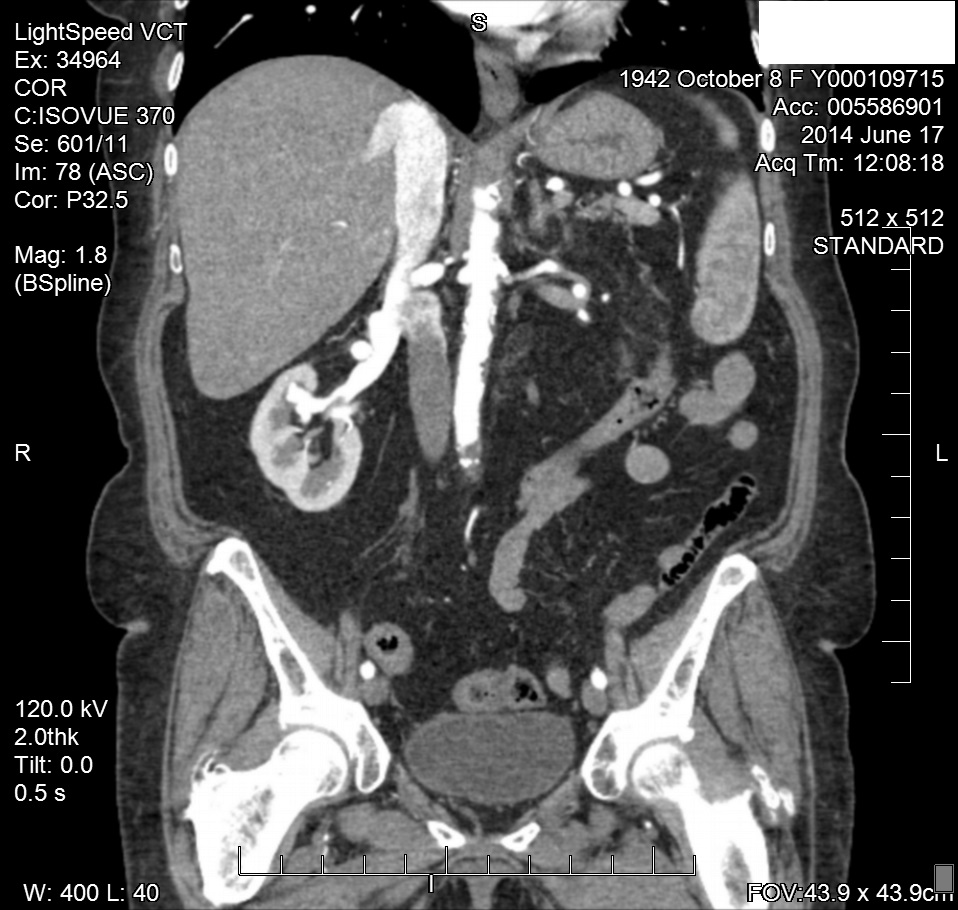

Two months later, the patient was referred to the radiology department for additional imaging with CTA. The CTA of the abdomen verified the “banded” appearance of both renal arteries consistent with FMH. The CTA also verified the angiographic findings of a right renal artery helium AV fistula or AV malformation. Since the bilateral renal artery angioplasties, the patient’s blood pressures have remained in the 130/70mm Hg range (Figure 7-9).

Figure 4 CTA of RRA FMD.